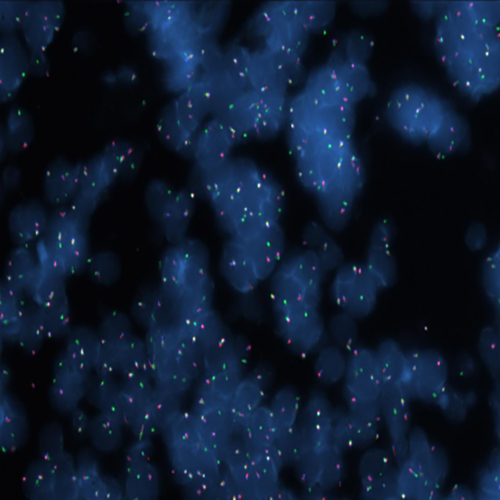

Hybridization of MYC TC break probe to a tissue section showing abarrant pattern (1GBR1G1BR).

Rearrangements of the proto oncogene MYC c-myc) have been consistently found in Burkitt's lymphoma tumor cells. In cases with the common t(8;14) chromosomal translocation, the MYC gene is translocated to chromosome 14 and rearranged with the immunoglobulin heavy chain genes; the breakpoint occurs 5' to the MYC gene and may disrupt the gene itself. In Burkitt's lymphoma showing the variant t(2;8) or t(8;22) translocations, the genes coding for the k and l immunoglobulin light chain are translocated to v-myc avian myelocytomatosis viral oncogene homolog (MYC or c-myc) chromosome 8. The MYC (8q24) Break probe is optimized to detect rearrangements involving the 8q24 locus in a triple-color, split assay on formalin fixed paraffin embedded tissue.